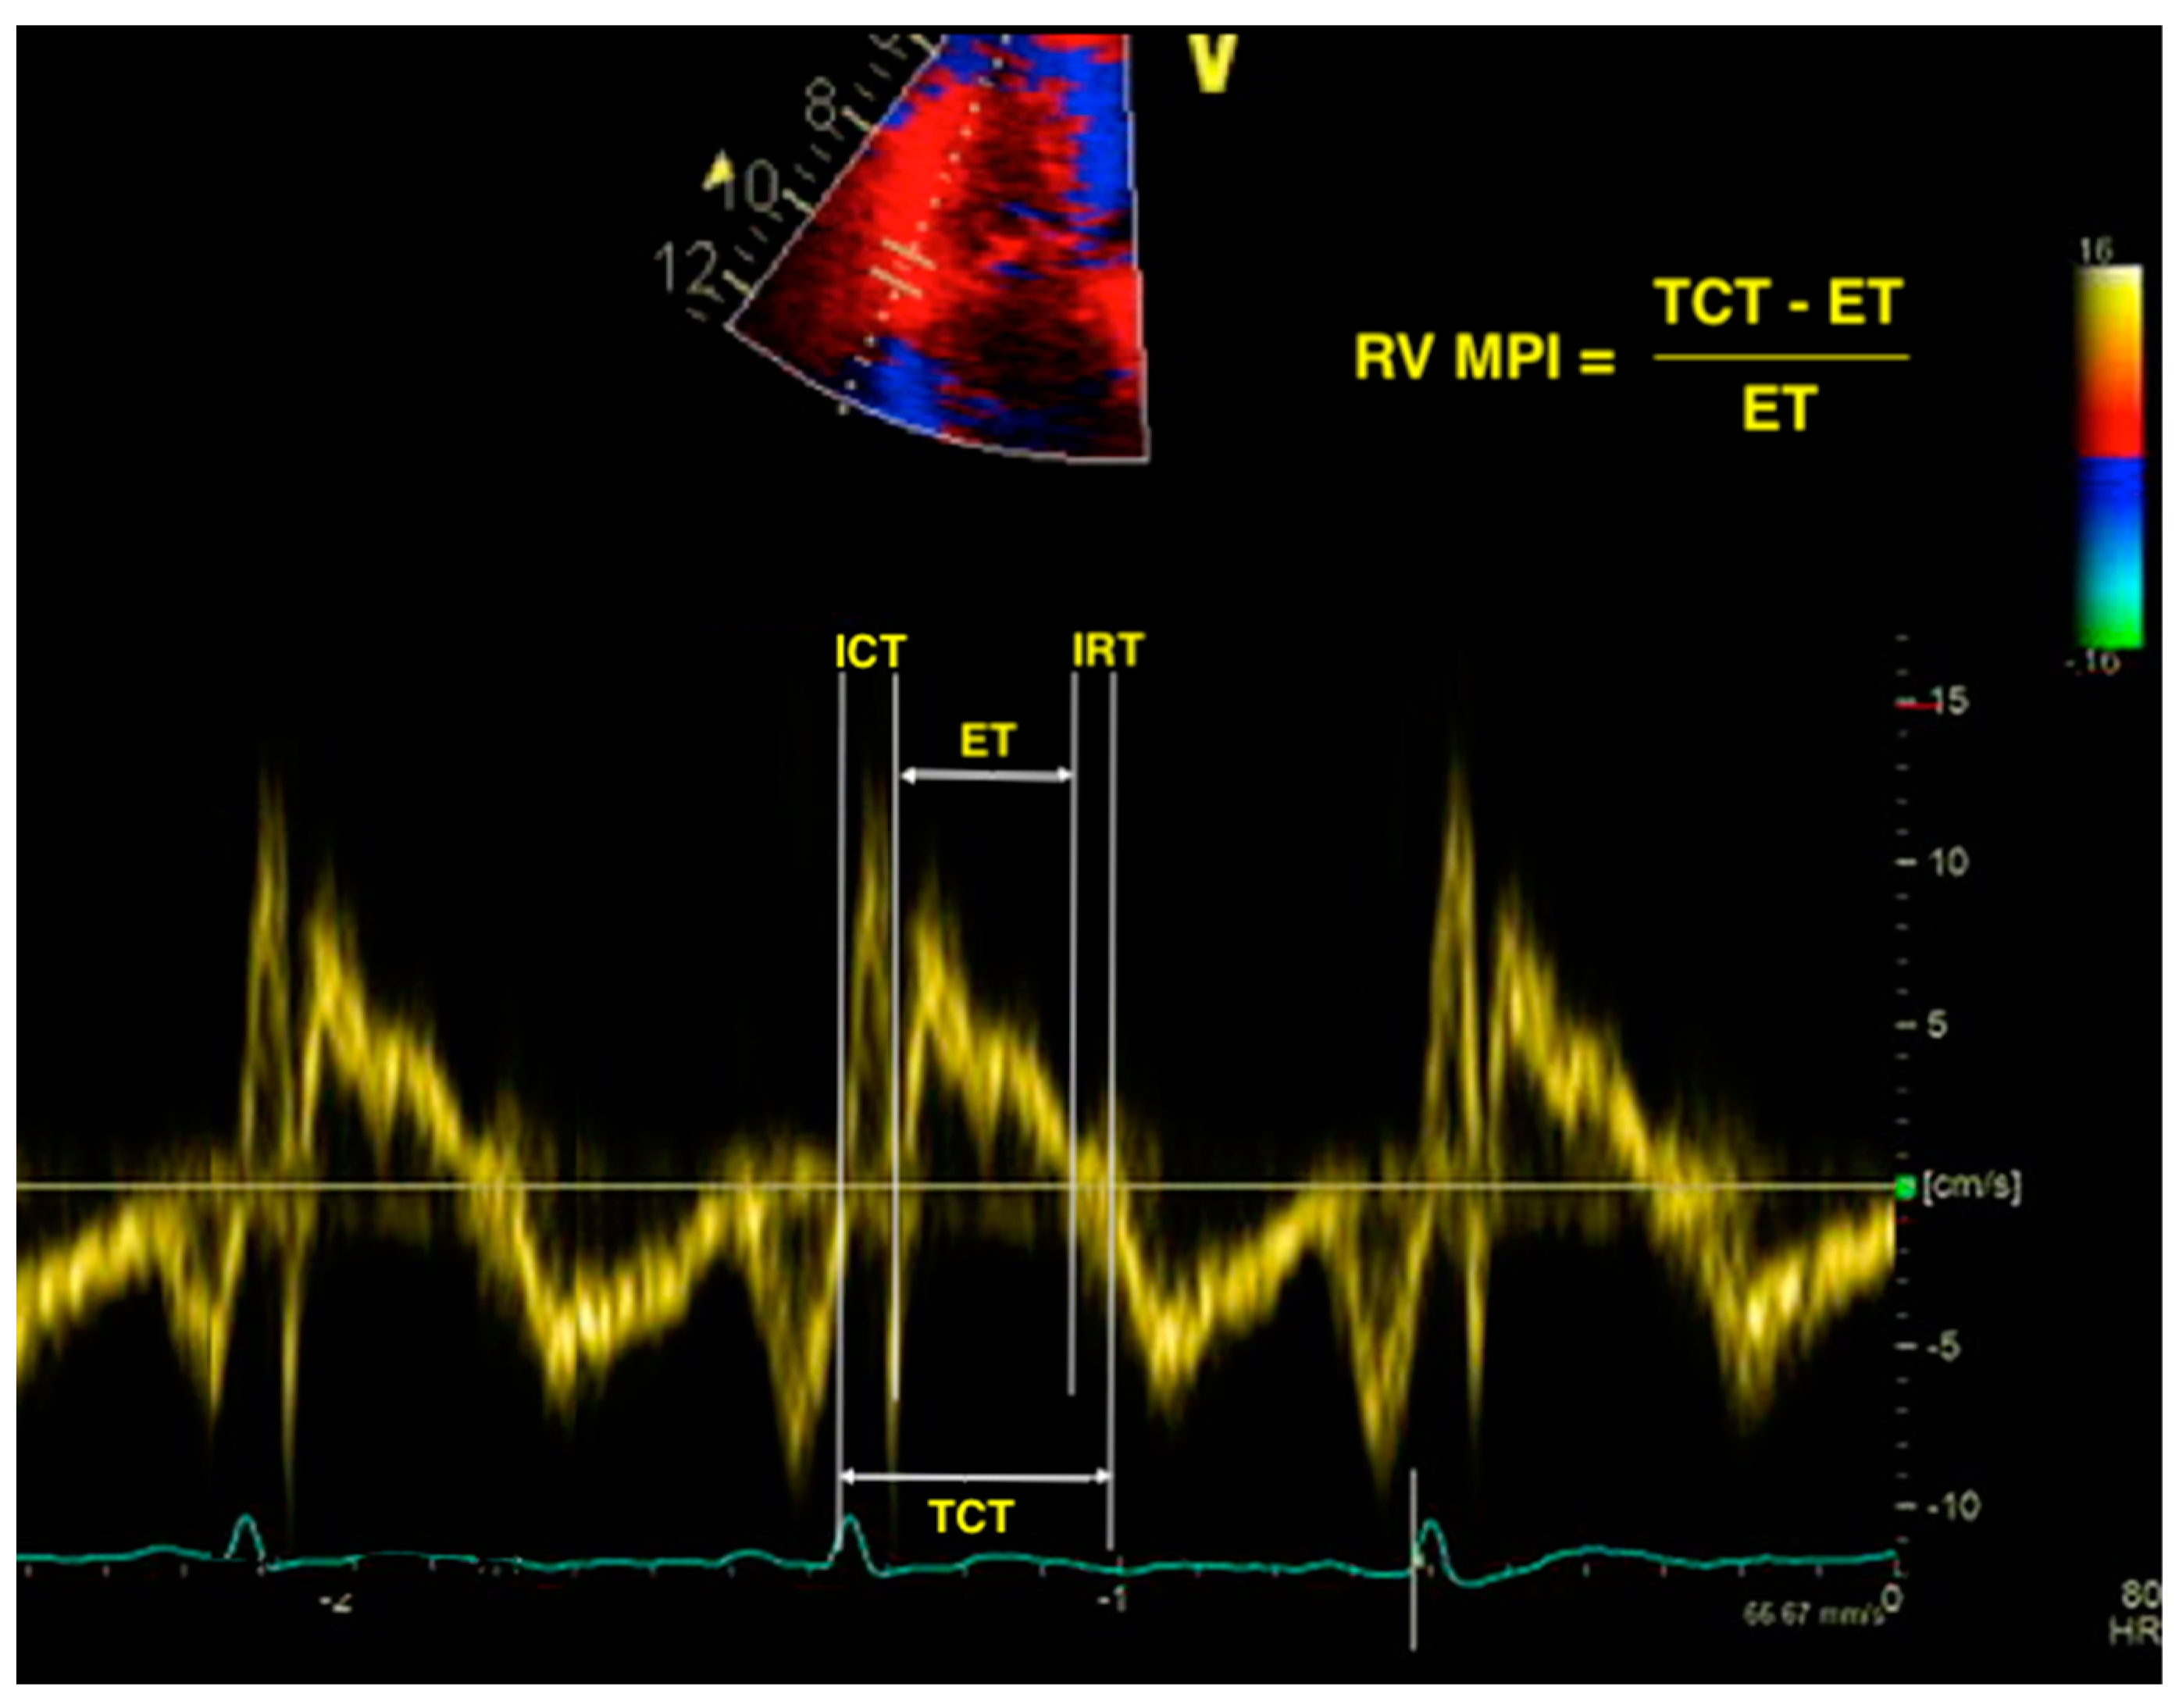

5 Steps to Identify Diastolic Dysfunction in Echo Cardioserv Rv Failure Echo Visual examination is the most. Markedly elevated cvp (central venous pressure) usually indicates rv failure in the absence of an obvious alternative. Due to the complex anatomy of the rv, echocardiographic evaluation of rv function is often difficult. Mortality as high as lv failure. The presence of rvd in patients with pah is a strong predictor of adverse outcomes and. Rv Failure Echo.